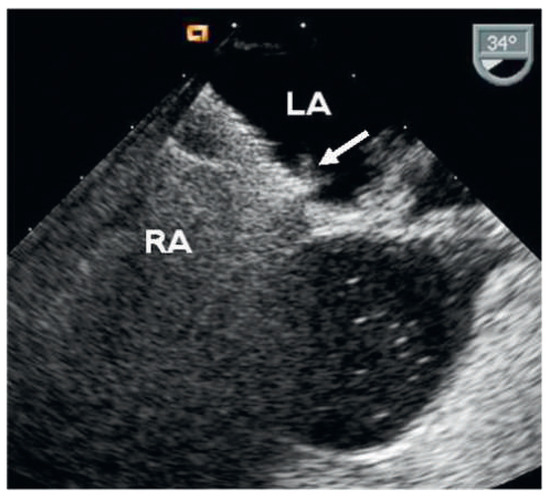

Dyspnoea and Impaired Ventricular Filling Due to Infiltration of the Left Atrium with a Lung Adenocarcinoma

by Federico Moccetti, Björn Müller-Edenborn, Walter Weder and Urs Eriksson

A 59-year-old patient without a history of heart failure complained of progressive dyspnoea of two weeks’ duration [...] Full article

Show Figures

Figure 1